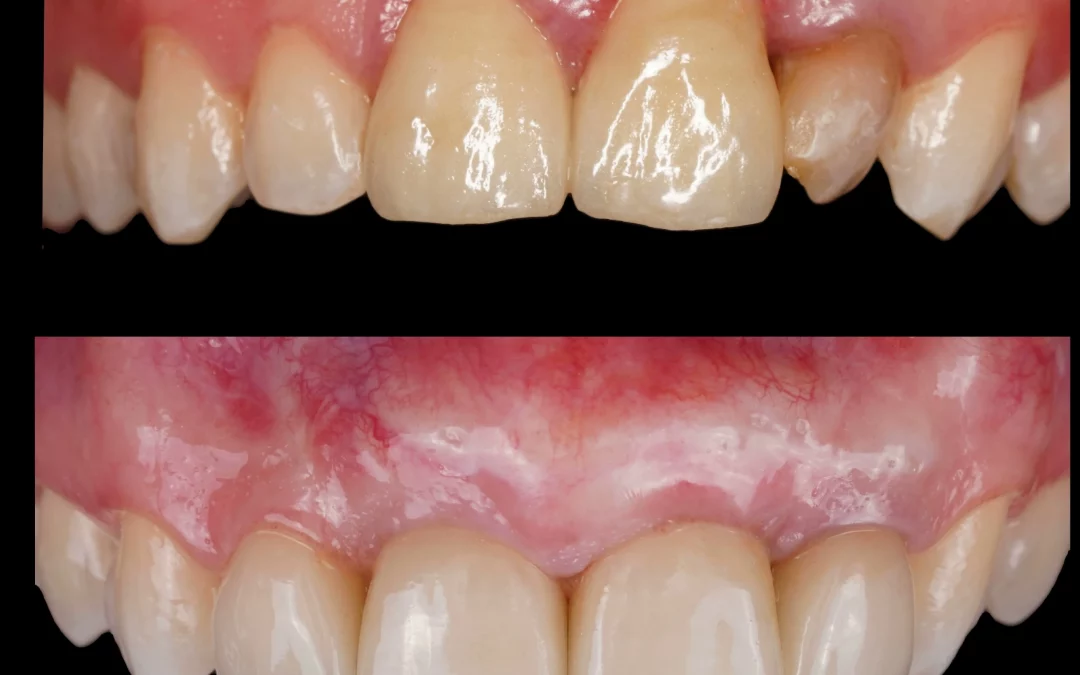

Ренат Ризванов | Клинический кейс RR-40

Небольшой рекол в 1 год после имплантации в область адентии двоек на верхней челюсти. - Имплантация MIS C1 узкая платформа. - Connect абатменты. #mis #misC1 #connect...